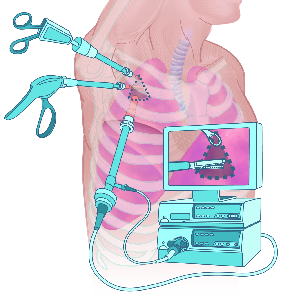

Über 860 Stichworte mit 120 Illustrationen auf 400 Seiten machen aus dem Lexikon der Lunge ein

wertvolles Werk.

Detailreiche Fotografien aus der medizinischen Praxis ergänzen die Texte; moderne, genaue,

wissenschaftliche Zeichnungen geben Einblick in die Anatomie und die Funktion der Lunge und

anderer Organe.